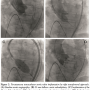

Case Report. An 83-year-old man was admitted to our department for dyspnea (New York Heart Association class III) and paroxysmal nocturnal dyspnea. The patient had persistent atrial fibrillation, cerebrovascular disease, and severe restrictive pulmonary disease. Transthoracic echocardiogram showed a rheumatic disease with severe mitral stenosis (mitral valve area of 1.0 cm2, maximum gradient of 39 mmHg, mean of 13 mmHg) and mild mitral regurgitation and severe aortic stenosis with moderate aortic regurgitation (maximum transvalvular aortic gradient of 110 mmHg, mean of 66 mmHg, aortic valve area of 0.8 cm2). Systolic pulmonary pressure was 95 mmHg at cardiac catheterization (mean of 52 mmHg) and mean wedge pressure was 28 mmHg. Left ventricular ejection fraction was 60%. At transesophageal echocardiogram, the Wilkins score was 10 and the aortic annulus was 22 mm. Because of high surgical risk (logistic EuroSCORE of 32% and STS score of 10%), a percutaneous treatment of both mitral and aortic valvulopathies was planned. We decided to perform the mitral balloon valvuloplasty first to reduce the pulmonary pressure and to increase the cardiac output and thus to improve the safety of transcatheter aortic valve implantation (TAVI). Moreover, because the patient was unquestionably refused even for back-up surgery, we preferred to make sure that the mitral valvuloplasty was successful before proceeding with the TAVI. We aimed to avoid wasting a costly prosthesis because of mitral valvuloplasty failure. The mitral balloon valvuloplasty was performed with antegrade transseptal approach. By progressive inflations of a 28 mm Inoue balloon catheter (Toray Industries Inc., Tokyo, Japan), transvalvular mitral gradient dropped from 15 mmHg to 7 mmHg, and the valve area improved either at invasive (1.5 cm2) or at transthoracic echo evaluation (1.6 cm2) with moderate regurgitation (Figure 1).